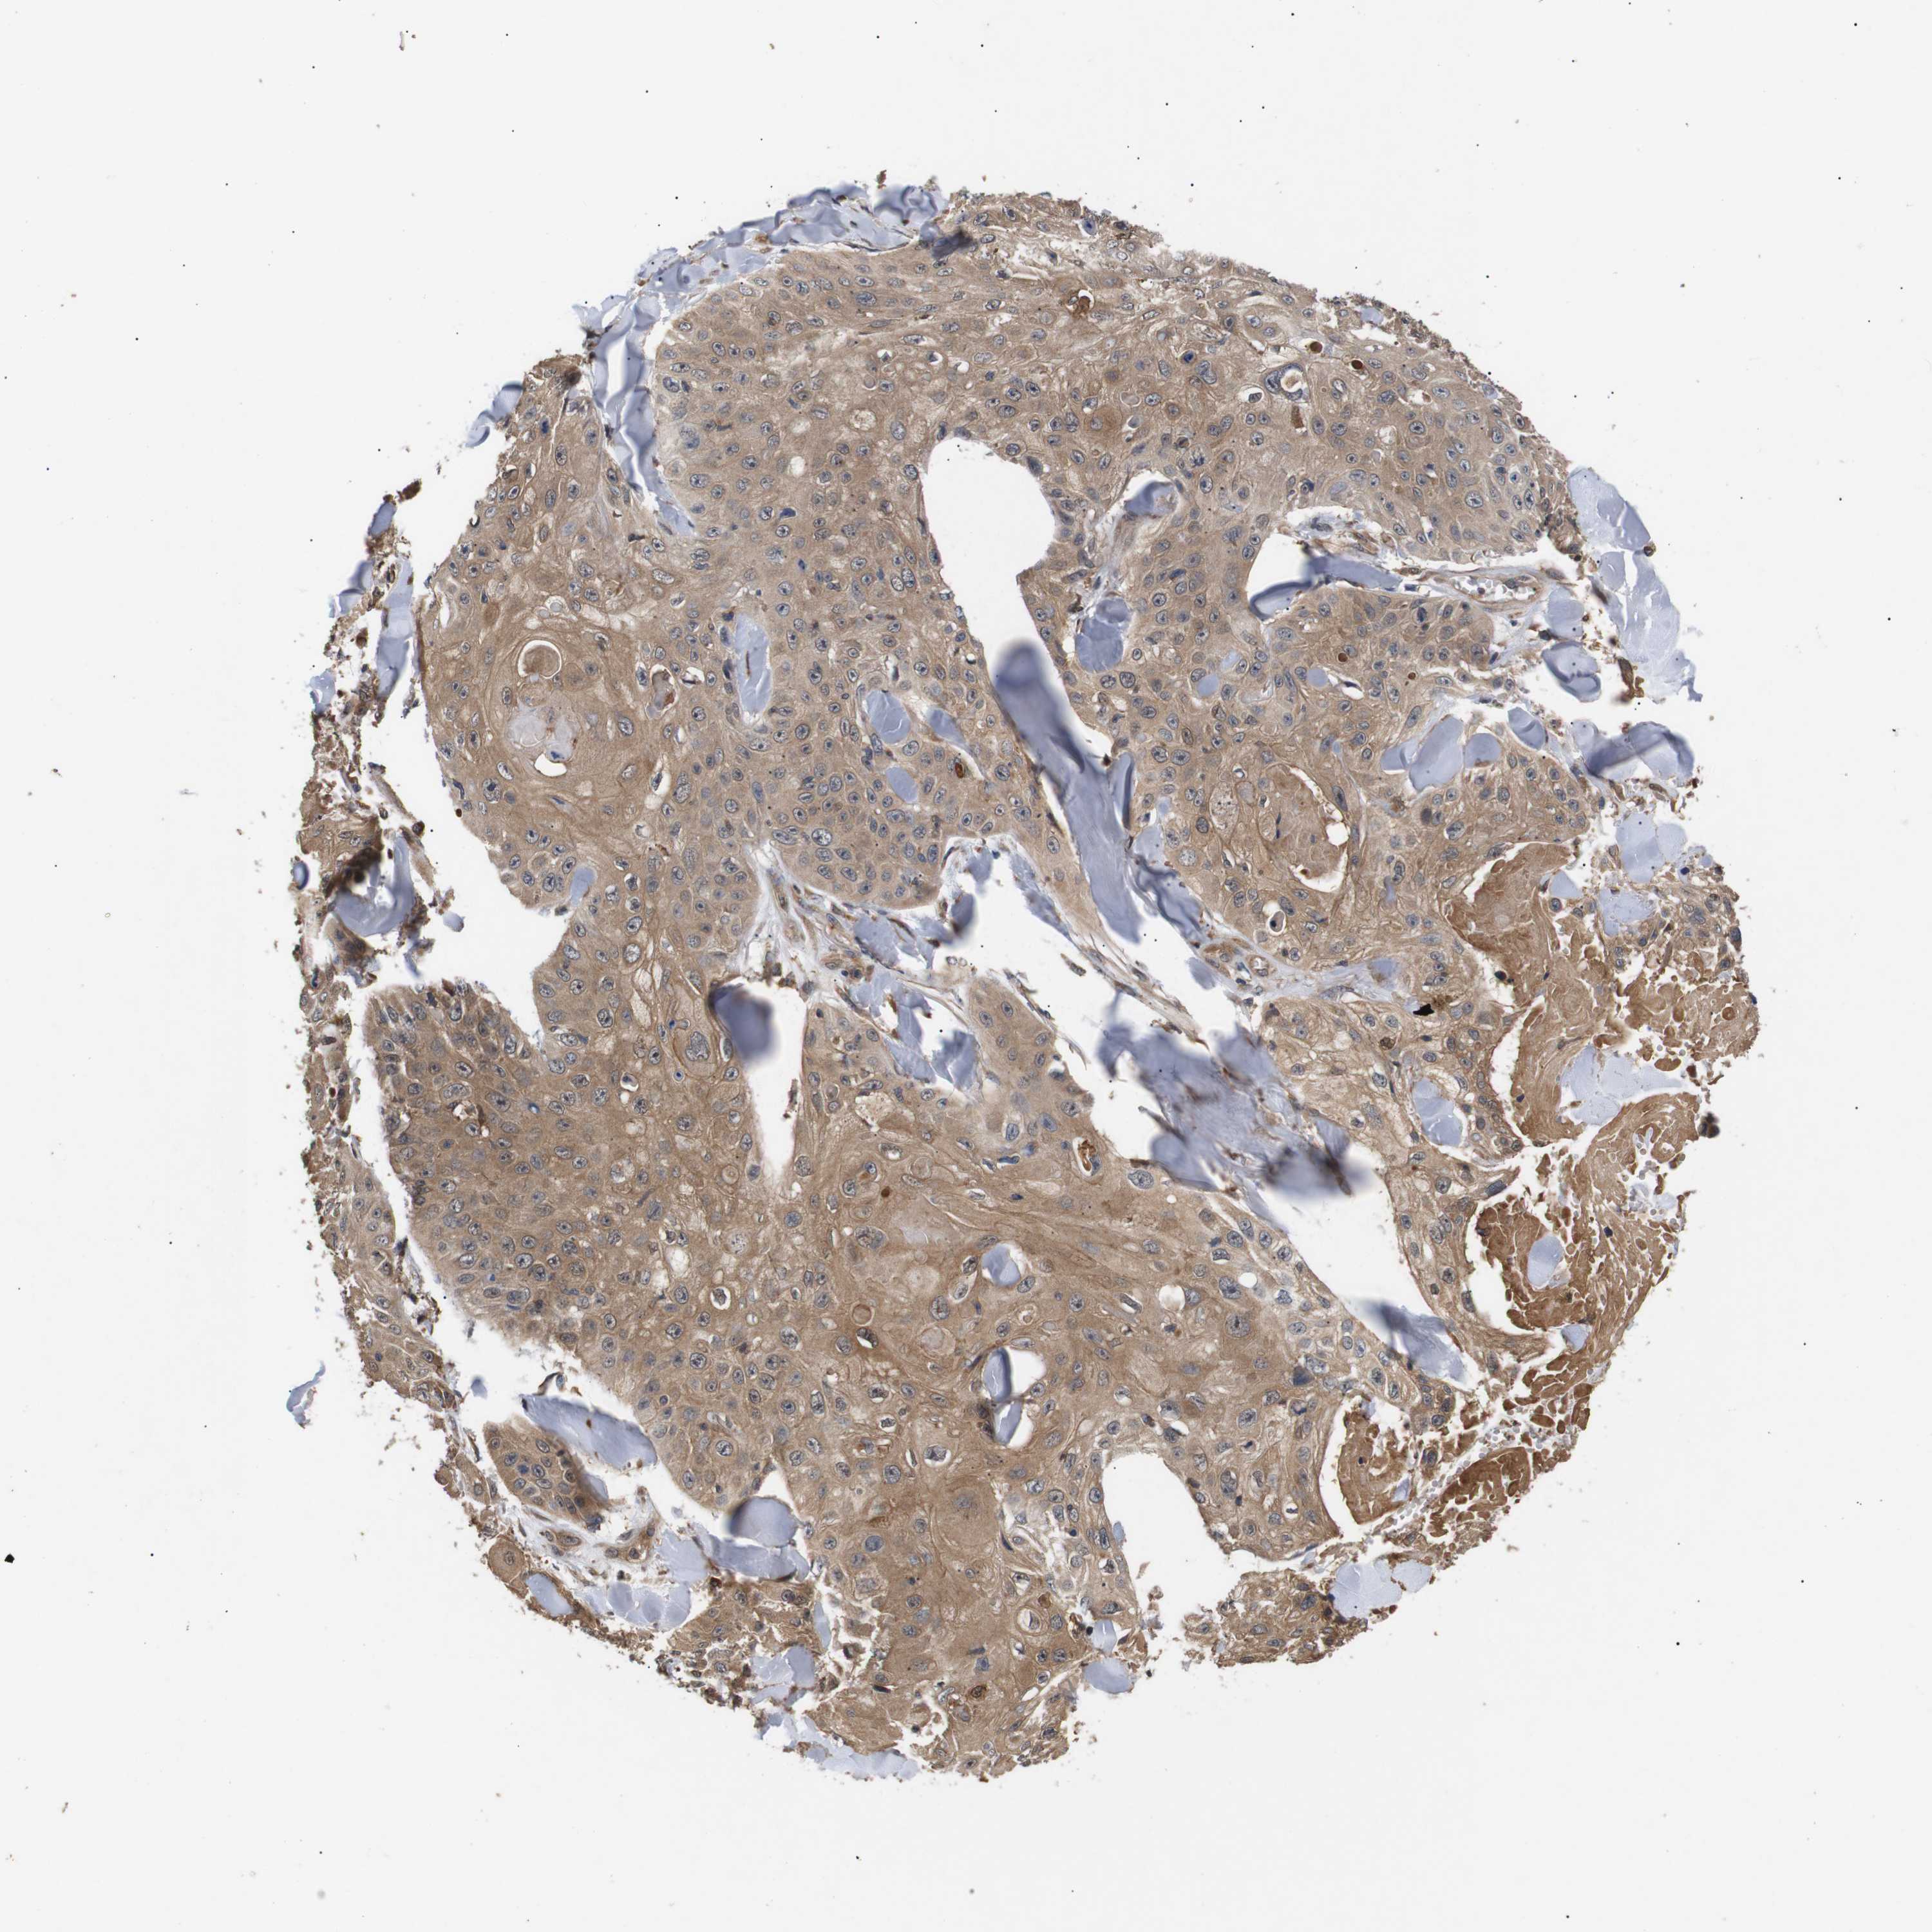

Basal cell and squamous cell cancer

SKIN CANCER - Protein expressioni

A mouse-over function shows sample information and annotation data. Click on an image to view it in a full screen mode. Samples can be filtered based on level of antibody staining by selecting one or several of the following categories: high, medium, low and not detected. The assay and annotation is described here.

Antibody stainingi

Antibody staining in the annotated cell types in the current human tissue is reported as not detected, low, medium, or high, based on conventional immunohistochemistry profiling in selected tissues. This score is based on the combination of the staining intensity and fraction of stained cells.

Each image is clickable and will lead to virtual microscopy that enables deeper exploration of all samples and also displays staining intensity scores, fraction scores and subcellular localization as well as patient and tissue information for each sample.

Antibody CAB010162

Antibody CAB025656

Staining

High

Medium

Low

Not detected

Intensity

Strong

Moderate

Weak

Negative

Quantity

>75%

75%-25%

<25%

None

Location

Nuclear

Cytoplasmic/membranous

Cytoplasmic/membranous,nuclear

Squamous cell carcinoma, NOS

Basal cell carcinoma

Squamous cell carcinoma, metastatic, NOS